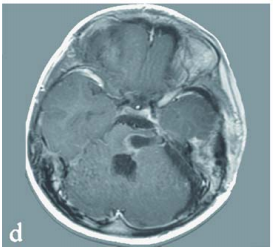

年仅7岁的浩浩偶尔抱怨自己头痛,但这一症状却被工作繁忙的父母忽视了,直到某天浩浩突然晕倒,住院2天后更是恶化为意识不清、无法说话!而这一切,全是因为脑干出血。 脑干是人体的生...

宝宝,你再看一眼爸爸妈妈好吗?病床旁,站着一对心碎的父母。两天前还一切正常、活蹦乱跳的儿子小奈,如今竟已无法开口说话,成了对外界毫无反应的植物人。 病情的恶化超乎他们想象...